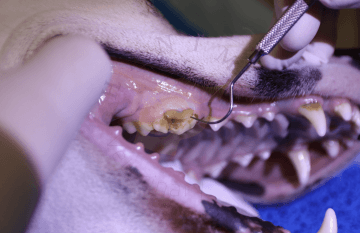

Když si pes zlomí zub a obnaží dřeň, bakterie a zbytky z úst proniknou do středu zubu. V důsledku toho se rozvine bolestivý zánět dřeně (pulpitida), který nakonec způsobí odumírání nervů a krevních cév (nekróza dřeně). Bakterie pronikají ven z kořenového hrotu (špička kořene obklopená kostí) a infikují kost kolem kořene (apikální parodontitida). Pulpitida i apikální parodontitida jsou velmi bolestivé. Vzhledem k tomu, že infekce zubu a následně také infekce kosti kolem kořene je vysoce pravděpodobná, zlomené zuby s obnažením dřeně by měly být co nejdříve ošetřeny buď standardní terapií kořenových kanálků tj. endodonticky, nebo extrakcí.

Léčba kořenových kanálků je méně invazivní než extrakce a ve většině případů terapie kořenových kanálků zachrání zub po zbytek života psa. Alternativou je vytržení zubu. U zubu s dobrou alveolárnou podporou, tj. kromě obnažené pulpy jinak zdravý zub, to vyžaduje preparaci měkkých tkání a případně odstranění/odbroušení alveolární kosti. To všechno nese sebou zvýšené poškození měkkých a tvrdých tkání v dutině ústní a s tím spojená delší doba rekonvalescence. Proto se na naší klinice, pokud je to možné, vždy snažíme zuby zachránit a to především zuby strategické - špičáky a zuby trhákového komplexu.